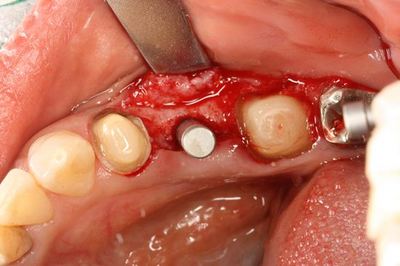

インプラントの埋入を終えました。

![]()

インプラントフィクスチャーの上部です。

カバースクリュー高さ0.5mmで封鎖します。